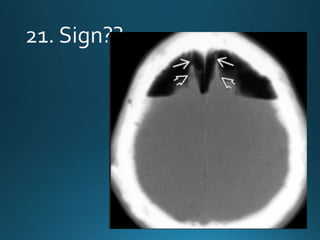

hydrocephalus